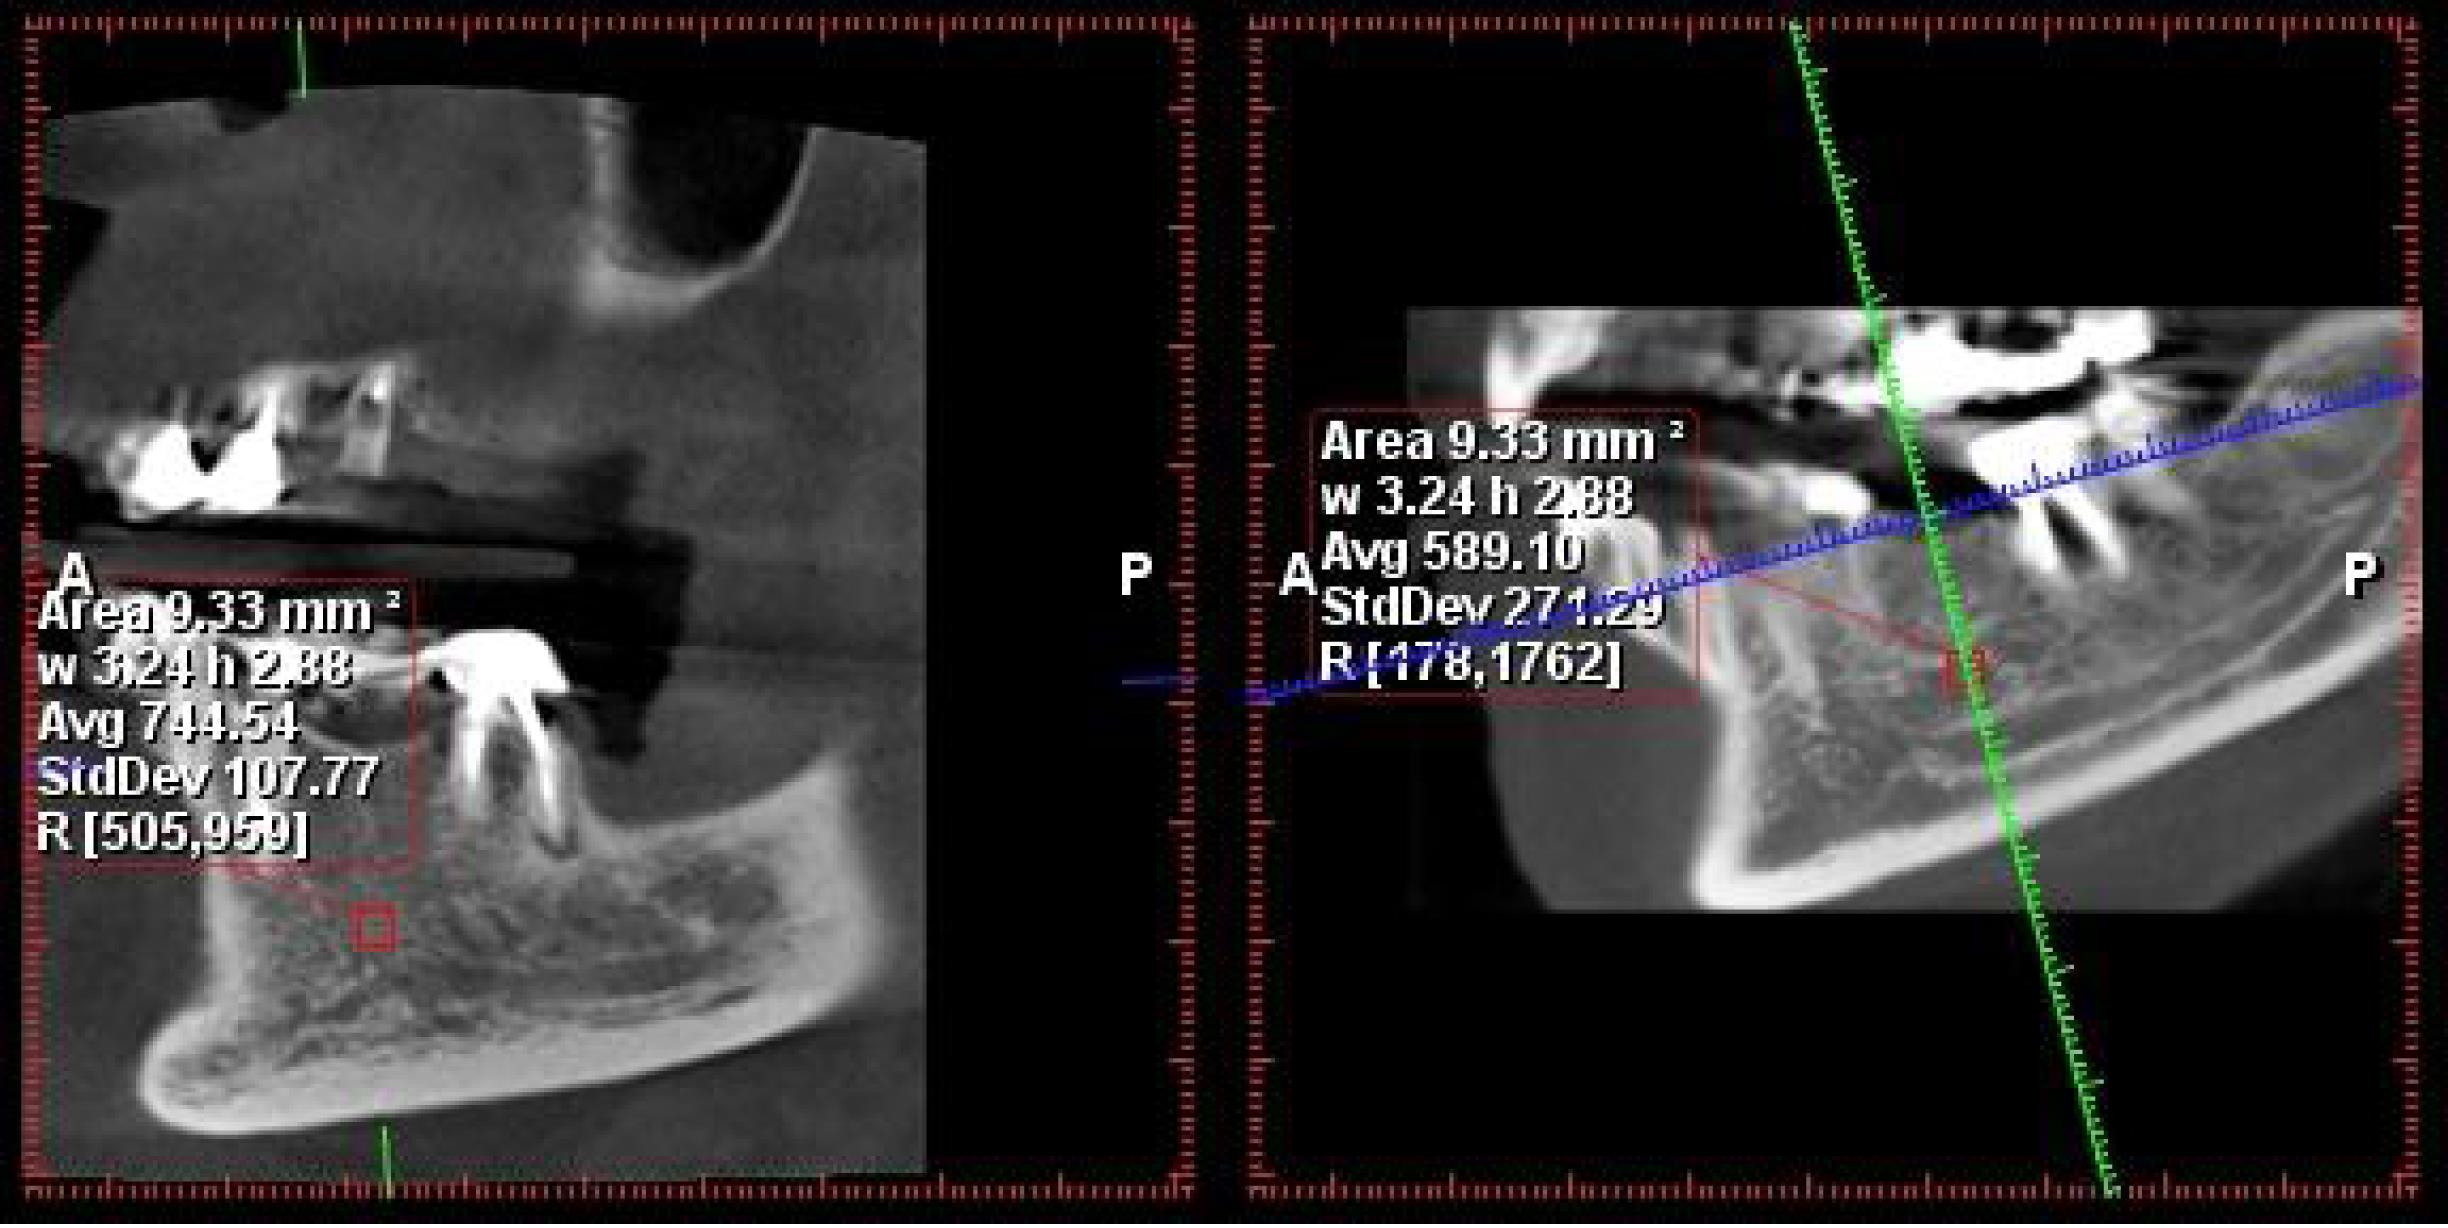

A specific measurement protocol was employed in the Romexis Planmeca software. The defined measurement area was a uniform mass of 3 × 3 mm. Within this area, the software automatically calculated the average Hounsfield numbers (as a measure of radiodensity) and presented them as an average value (Figures 1 and 2).

The measurement of bone density in the posterior mandibular region

The measurement of bone density in the posterior maxilla region